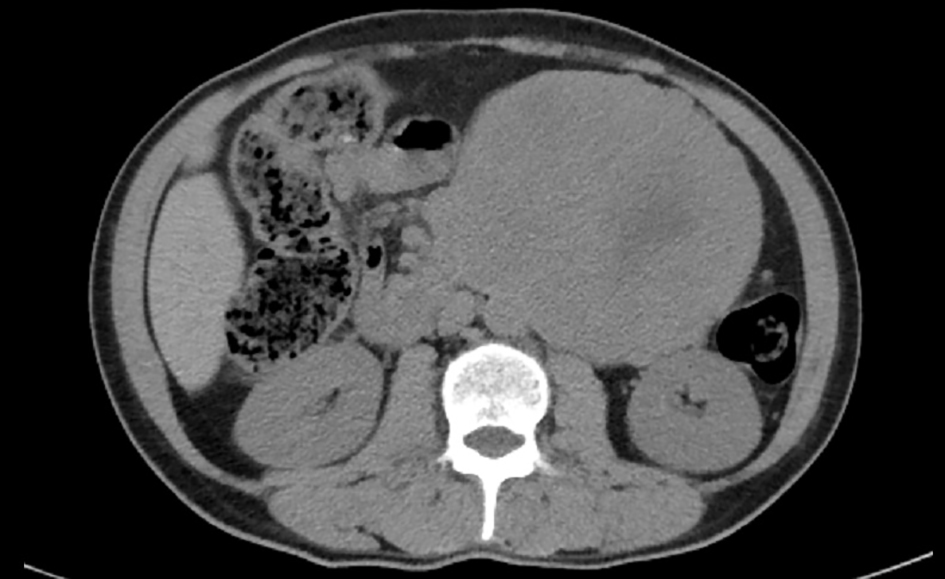

The patient was a middle-aged man, 45 years old, weighing 61 kg. The mass was found when the patient underwent a physical check-up 1 year ago. The mass had no tenderness, no abdominal pain or abdominal distension. No headache, dizziness, palpitations, fever or other discomfort, and self-sensing sweating were reported. No treatment was given at this stage. Recently, the patient felt that the lump gradually increased in size, and was admitted to hospital for additional examination. The anamnesis was hypertension for half a year, with the maximum blood pressure up to 180/110 mm Hg and no regular intake of antihypertensive drugs. Physical examination showed body temperature (T) 36.4 °C, heart rate (P) 62 times/min, respiratory rate (R) 18 times/min, and blood pressure (bp) 154/98 mm Hg. The abdomen was bulging. A lump was palpable, with the diameter of about 20 cm in the left abdomen. Biochemically test results showed urine vanilla mandelic acid (VMA) 528.69 µmol/24 h (normal range: 15.66 - 85.88), urine methoxylated norepinephrine in total 1,957.65 µg/24 h (normal range: 119 - 451), normal urinary methoxyprogesterine in total, normal blood cortisols (at 0:00, 8:00 am, and 16:00 pm), and the normal rest test items. In terms of clinical imaging result, the abdominal CT [6] showed a lump with the size of about 11.4 cm (AP), 110.9 cm (RL), and 15.8 cm (SI) in the left side of the abdominal cavity (Fig. 1); cardiac color Doppler showed left ventricular hypertrophy, and left ventricular diastolic dysfunction EF 72%; chest CT showed double emphysema and lung bulb; ECG and lung function were normal.

![]() Click for large image | Figure 1. Abdominal CT scan showing left abdominal mass. |